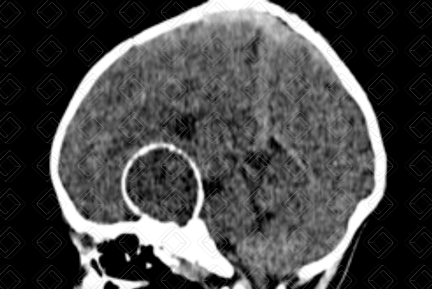

Texto alternativo para a imagem Figuras 1 e 2. Créditos: Dra. Elazir Mota - Rio de Janeiro/RJ

Descrição das figuras 1 e 2: Tomografia computadorizada de crânio evidenciando lesão selar e suprasselar predominantemente heterogênea, predominantemente hipodensa, com calcificação parietal, melhor apreciada na janela óssea (setas vermelhas).